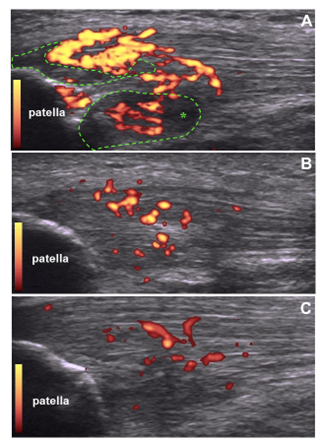

A 35-old year healthy Caucasian football player man presented with a 3years history of anterior knee pain and tenderness in his right patellar tendon insertion. He referred a constant dull aching pain with walking, forcing to discontinue sport because of the severity of his pain. He has been previously treated with conservative therapy and with platelet-rich plasma (PRP) injections; however his pain did not improve. At presentation, pain was rated as 7 out of 10 on Visual Analogue Scale (VAS). Color Doppler ultrasound examination revealed signs of tendinosis with significant neovascularity, formed by immature tortuous and dilated vessels into intratendinous mass (Figure 1A). Furthermore, color Doppler scans showed areas of intratendinousedema in the proximal patellar-tendon interface (Figure 1A). After discussing the various treatment options, the patient opted to try etamsylate injection and signed an informed consent. Lidocaine was infiltrated into the skin overlying the right patellar tendon. 4ml etamsylate (Dicynone®, Sanofi-Aventis. France) were injected under ultrasound guidance into peritendinous patellar tendon tissue. The procedure was uneventful. At 2weeks follow-up visit, patient reported a marked improvement of his pain (VAS was rated as 2), and color Doppler ultrasound scans showed a significant reduction of neovessels and disappearance of tendinous edema (Figure 1B). Furthermore, at 4weeks tendon hypervascularity decreased (Figure 1C) and pain strongly ameliorated (VAS=1). Patient could return to his previous level of sport without any restrictions.

Figure 1 The presence of neovessels is detected in the patellar tendon using color Doppler ultrasound. Longitudinal scans taken before (A) and after two (B) and four weeks(C) of etamsylate injection. Diminution of hypervascularity is demonstrated after injection of etamsylate. Note the reduction of edema (*) after two weeks of treatment.